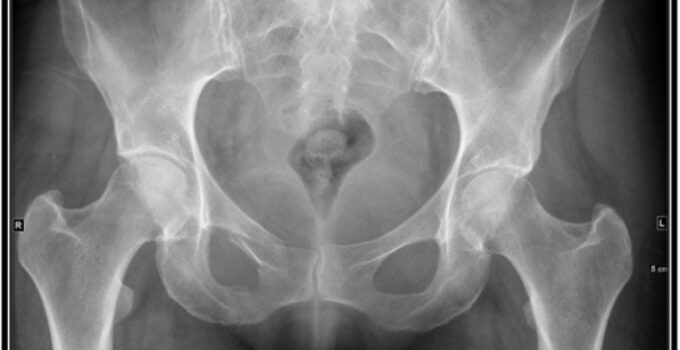

Pelvis Röntgeni

Leğen kemiği röntgeni her iki kalçanın etrafındaki kemiklerin röntgenidir. Pelvis bacakları vücuda bağlar.

Vücudunuzun bölümlerinin kalınlığı değişir, bu nedenle farklı miktarlarda radyasyon alırlar. Kemiklerinizdeki kalsiyum daha fazla radyasyon alır, bu nedenle kemikleriniz röntgende beyaz görünür. Yumuşak dokular daha az radyasyon alır, bu nedenle farklı gri tonlarında görünürler. Hava siyah görünür. Kırık bir kemiğiniz varsa, kemik beyaz görünür ve kemiğin içinden geçen siyah bir çizgi kırığı gösterir.

Kırıklar, tümörler, kalça, pelvis ve üst bacaklardaki kemiklerin dejeneratif durumları.

Pelvik kırıklar, kalça ekleminin artriti, pelvis kemiklerinin tümörleri, sakroiliit (sakrumun ilium kemiğiyle birleştiği bölgenin iltihabı), ankilozan spondilit(omurga ve eklemin anormal sertliği)

alt omurganın artriti, pelvisinizin veya kalça ekleminizin şeklindeki anormallik.

Erkek pelvis röntgenleri ve kadın pelvis röntgenleri, erkekler ve kadınlar (veya doğumda kadın olarak atananlar ve doğumda erkek olarak atananlar) arasındaki kemik yapılarındaki farklılıkları gösterebilir. Yetişkin bir erkek leğen kemiği, kadın pelvisinden daha dardır. Yetişkin bir kadın pelvisi genellikle erkek pelvisinden daha geniştir. Erkek pelvis daha oval veya kalp şeklindedir. Dişi pelvis daha yuvarlaktır. Ayrıca, bir erkek pelvisinde kasık kemerinin açısı 90 dereceden azdır. Bir kadın pelvisindeki kasık kemerinin açısı 90 dereceden fazladır.